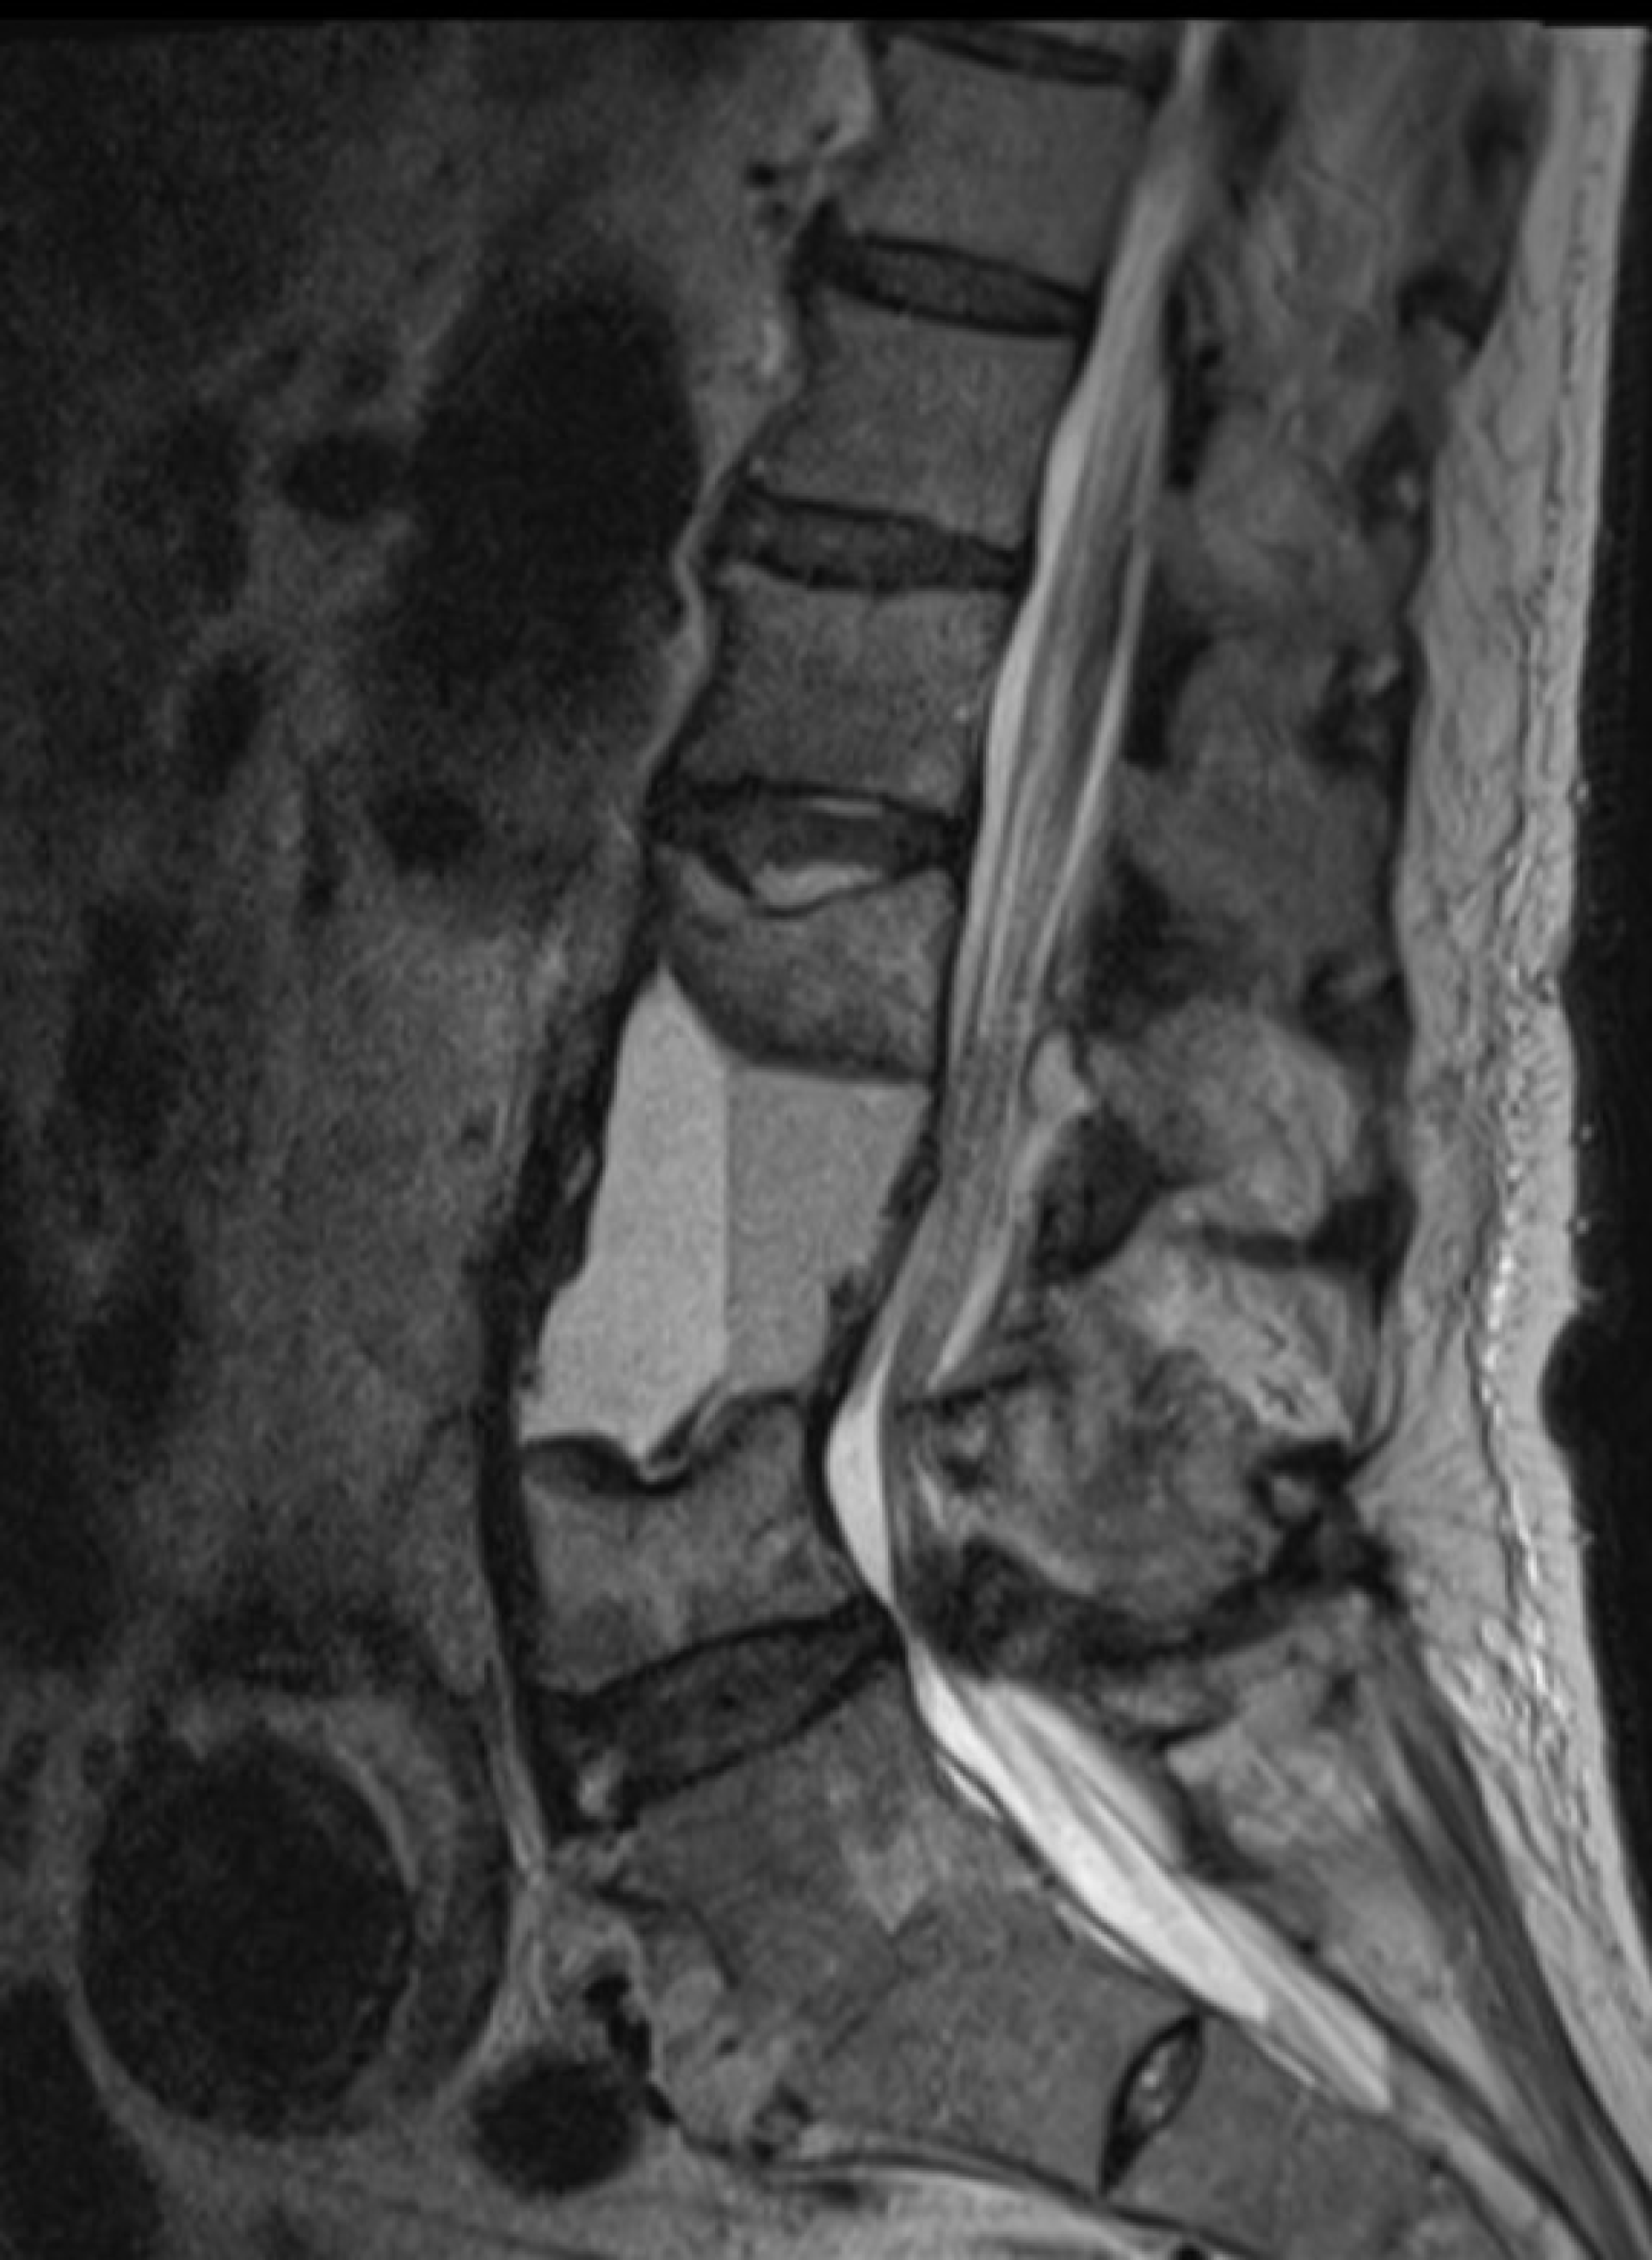

Onze casus betreft een 69-jarige zorgmijder die onder andere bekend was met een aortaprothese (EVAR), een doorgemaakte duodenumbloeding zes maanden eerder met op de destijds verrichte CT abdomen een normale wervelkolom (figuur 1) en sinds anderhalve maand toename van bekende lumbago. Door de huisarts was meermaals getracht een MRI van de wervelkolom te laten verrichten, maar patiënt was hier zowel lichamelijk als geestelijk nog niet toe ‘te mobiliseren’ geweest. Patiënt had een moeizame relatie met zijn huisarts en had over het algemeen weinig vertrouwen in hulpverleners waarmee hij frequent in conflict kwam. Er waren vermoedens op persoonlijkheidsproblematiek. Wat betreft de MRI had hij aangegeven daar niet in te durven, niet te kunnen liggen door de pijn, geen vervoer te hebben en überhaupt het nut van beeldvormend onderzoek niet in te zien. Even later werd patiënt ingestuurd naar de Spoedeisende Hulp vanwege koorts en rugpijn, alwaar bij lichamelijk onderzoek een parese van beide benen opviel. Ook bleek er sprake van urine-incontinentie waarbij er gedacht werd aan een reeds langer bestaand caudasyndroom. Laboratoriumonderzoek toonde verhoogde inflammatieparameters (bezinking 91 mm/uur; CRP 267 mg/l) en op een MRI van de wervelkolom werd een uitgebreide spondylodiscitis van L1 t/m L3 gezien met werveldestructie en abcesvorming (figuur 2). Uit urine-, bloed- en latere peroperatieve kweken werd een ESBL E. Coli geïsoleerd. Patiënt kreeg boomstamverpleging en werd met meropenem en pijnstilling behandeld. Met als doel patiënt weer enige mobiliteit, vermindering van pijn en verbetering van kwaliteit van leven te kunnen bieden, werd besloten de lumbale wervelkolom te stabiliseren door middel van percutane fixatie middels schroeven en staven. Hierop had patiënt weliswaar meer bewegingsvrijheid, maar zijn krachtsverlies en slechte conditie waren dusdanig invaliderend dat hij zijn bed alsnog niet uitkwam. Verder persisteerde de koorts ondanks reeds meerdere weken intraveneuze antibiotische therapie. Er werd een PET-CT verricht ter evaluatie van eventuele betrokkenheid van de nabijgelegen EVAR. Dit leek niet het geval; wel was er sprake van een zich verder uitbreidende infectie. Na uitvoerig multidisciplinair overleg met collega’s van de geriatrie, orthopedie, neurologie, microbiologie, radiologie en infectiologie en vervolgens een second opinion in het academisch ziekenhuis bleek een tweede, zeer ingrijpende operatie vereist om de uitgebreide spondylodiscitis verder te behandelen.

Figuur 2. Sagittale MRI wervelkolom tijdens opname met uitgebreide spondylodiscitis L1 t/m L3 met werveldestructie, vloeistof-vloeistof spiegel bij abcesvorming en lumbale kanaalstenose